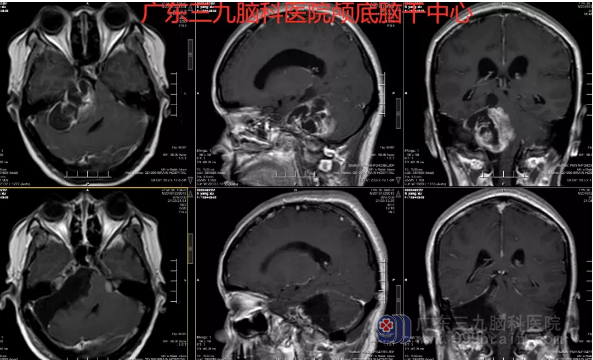

图2:术前术后MR示呈术后改变